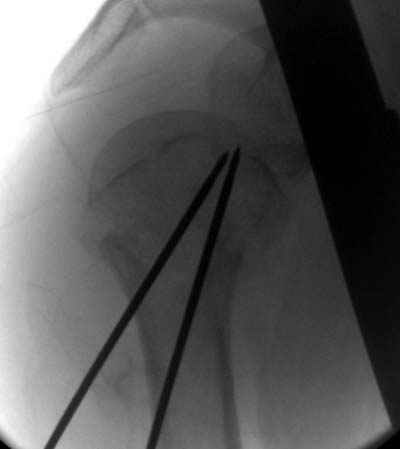

Здесь случай перелома-вывиха плеча, больному 56 лет, после "дважды" закрытой неудачной репозиции, опять же ургентно взяли в операционную, после полного общего обезболивания попытались сделать репозицию, и фиксацию провели спицами.

Больной находился в повязке, примерно напоминяющей косыночную, рекомендованы движения в локтевом суставе и маятниковые движения в плече, спицы удалены в три недели (были случаи миграции)

Больной амбулаторный, предупрежден на случай осложнения АВН головки.